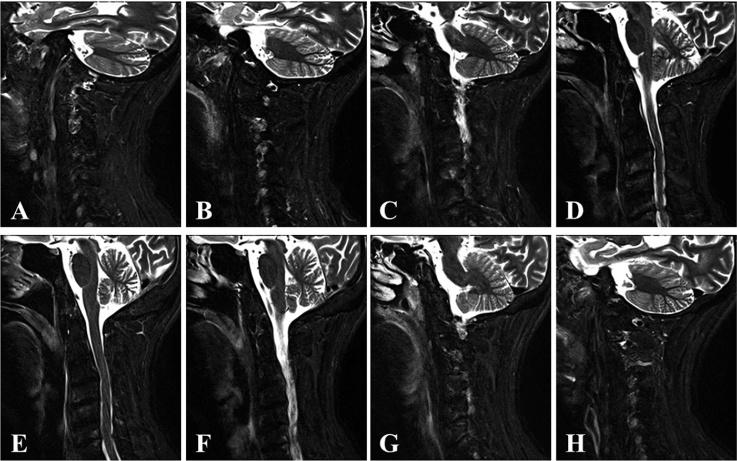

A 61-year-old man was admitted to our hospital with a severe occipital headache and sudden onset of neck stiffness. Neurological examination on admission revealed a high fever and cervical rigidity. Laboratory examination revealed a markedly elevated white blood cell count and C-reactive protein level, but cerebrospinal fluid studies revealed only a slight abnormality. A cervical computed tomography scan and its three-dimensional reconstruction detected a remarkable crown-like calcification surrounding the odontoid process. Cervical magnetic resonance imaging did not demonstrate strong direct compression of the cervical cord; however, the soft tissue surrounding the odontoid process was hyperintense on T2-weighted imaging with fat suppression. Based on the radiological findings, the patient was diagnosed with crowned dens syndrome and was immediately treated with non-steroidal anti-inflammatory drugs. The patient's condition drastically improved within 5days.

It was very interesting that the soft tissue surrounding the odontoid process was hyperintense on magnetic resonance T2-weighted imaging with fat suppression, and the signal change disappeared 2 weeks after the administration of oral non-steroidal anti-inflammatory drugs. We think that magnetic resonance imaging is useful for proving inflammation in patients with crowned dens syndrome.

一名61岁男性因严重枕部头痛和突然出现的颈部僵硬入住我院。入院时神经系统检查发现高热和颈部强直。实验室检查显示白细胞计数和C反应蛋白水平明显升高,但脑脊液检查仅显示轻微异常。颈椎计算机断层扫描及其三维重建检测到齿状突周围有明显的冠状钙化。颈椎磁共振成像未显示脊髓有强烈的直接压迫;然而,在脂肪抑制T2加权成像上,齿状突周围的软组织呈高信号。根据放射学检查结果,该患者被诊断为齿状突冠综合征,并立即接受非甾体抗炎药治疗。患者的病情在5天内大幅改善。

有趣的是,在脂肪抑制磁共振T2加权成像上,齿状突周围的软组织呈高信号,口服非甾体抗炎药2周后信号改变消失。我们认为磁共振成像有助于证实齿状突冠综合征患者的炎症。